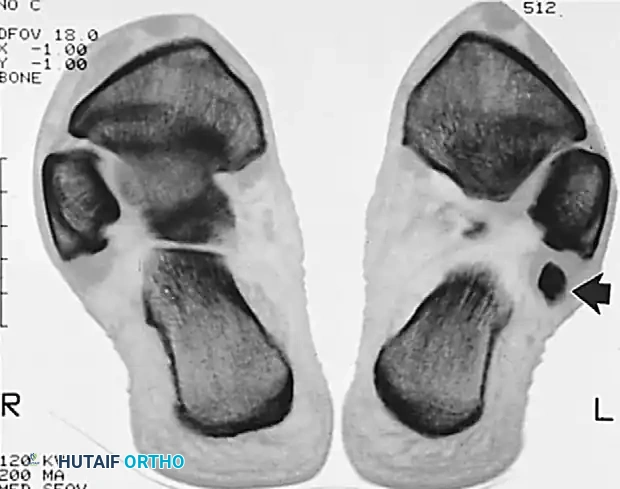

- Magnetic Resonance Imaging (MRI): The gold standard for evaluating tendon integrity, fluid within the tendon sheath (tenosynovitis), and the morphology of the retromalleolar groove.

MRI appearance of peroneal tendon rupture with extensive tenosynovitis.

Axial imaging demonstrating the relationship of the peroneal tendons within the retromalleolar groove.